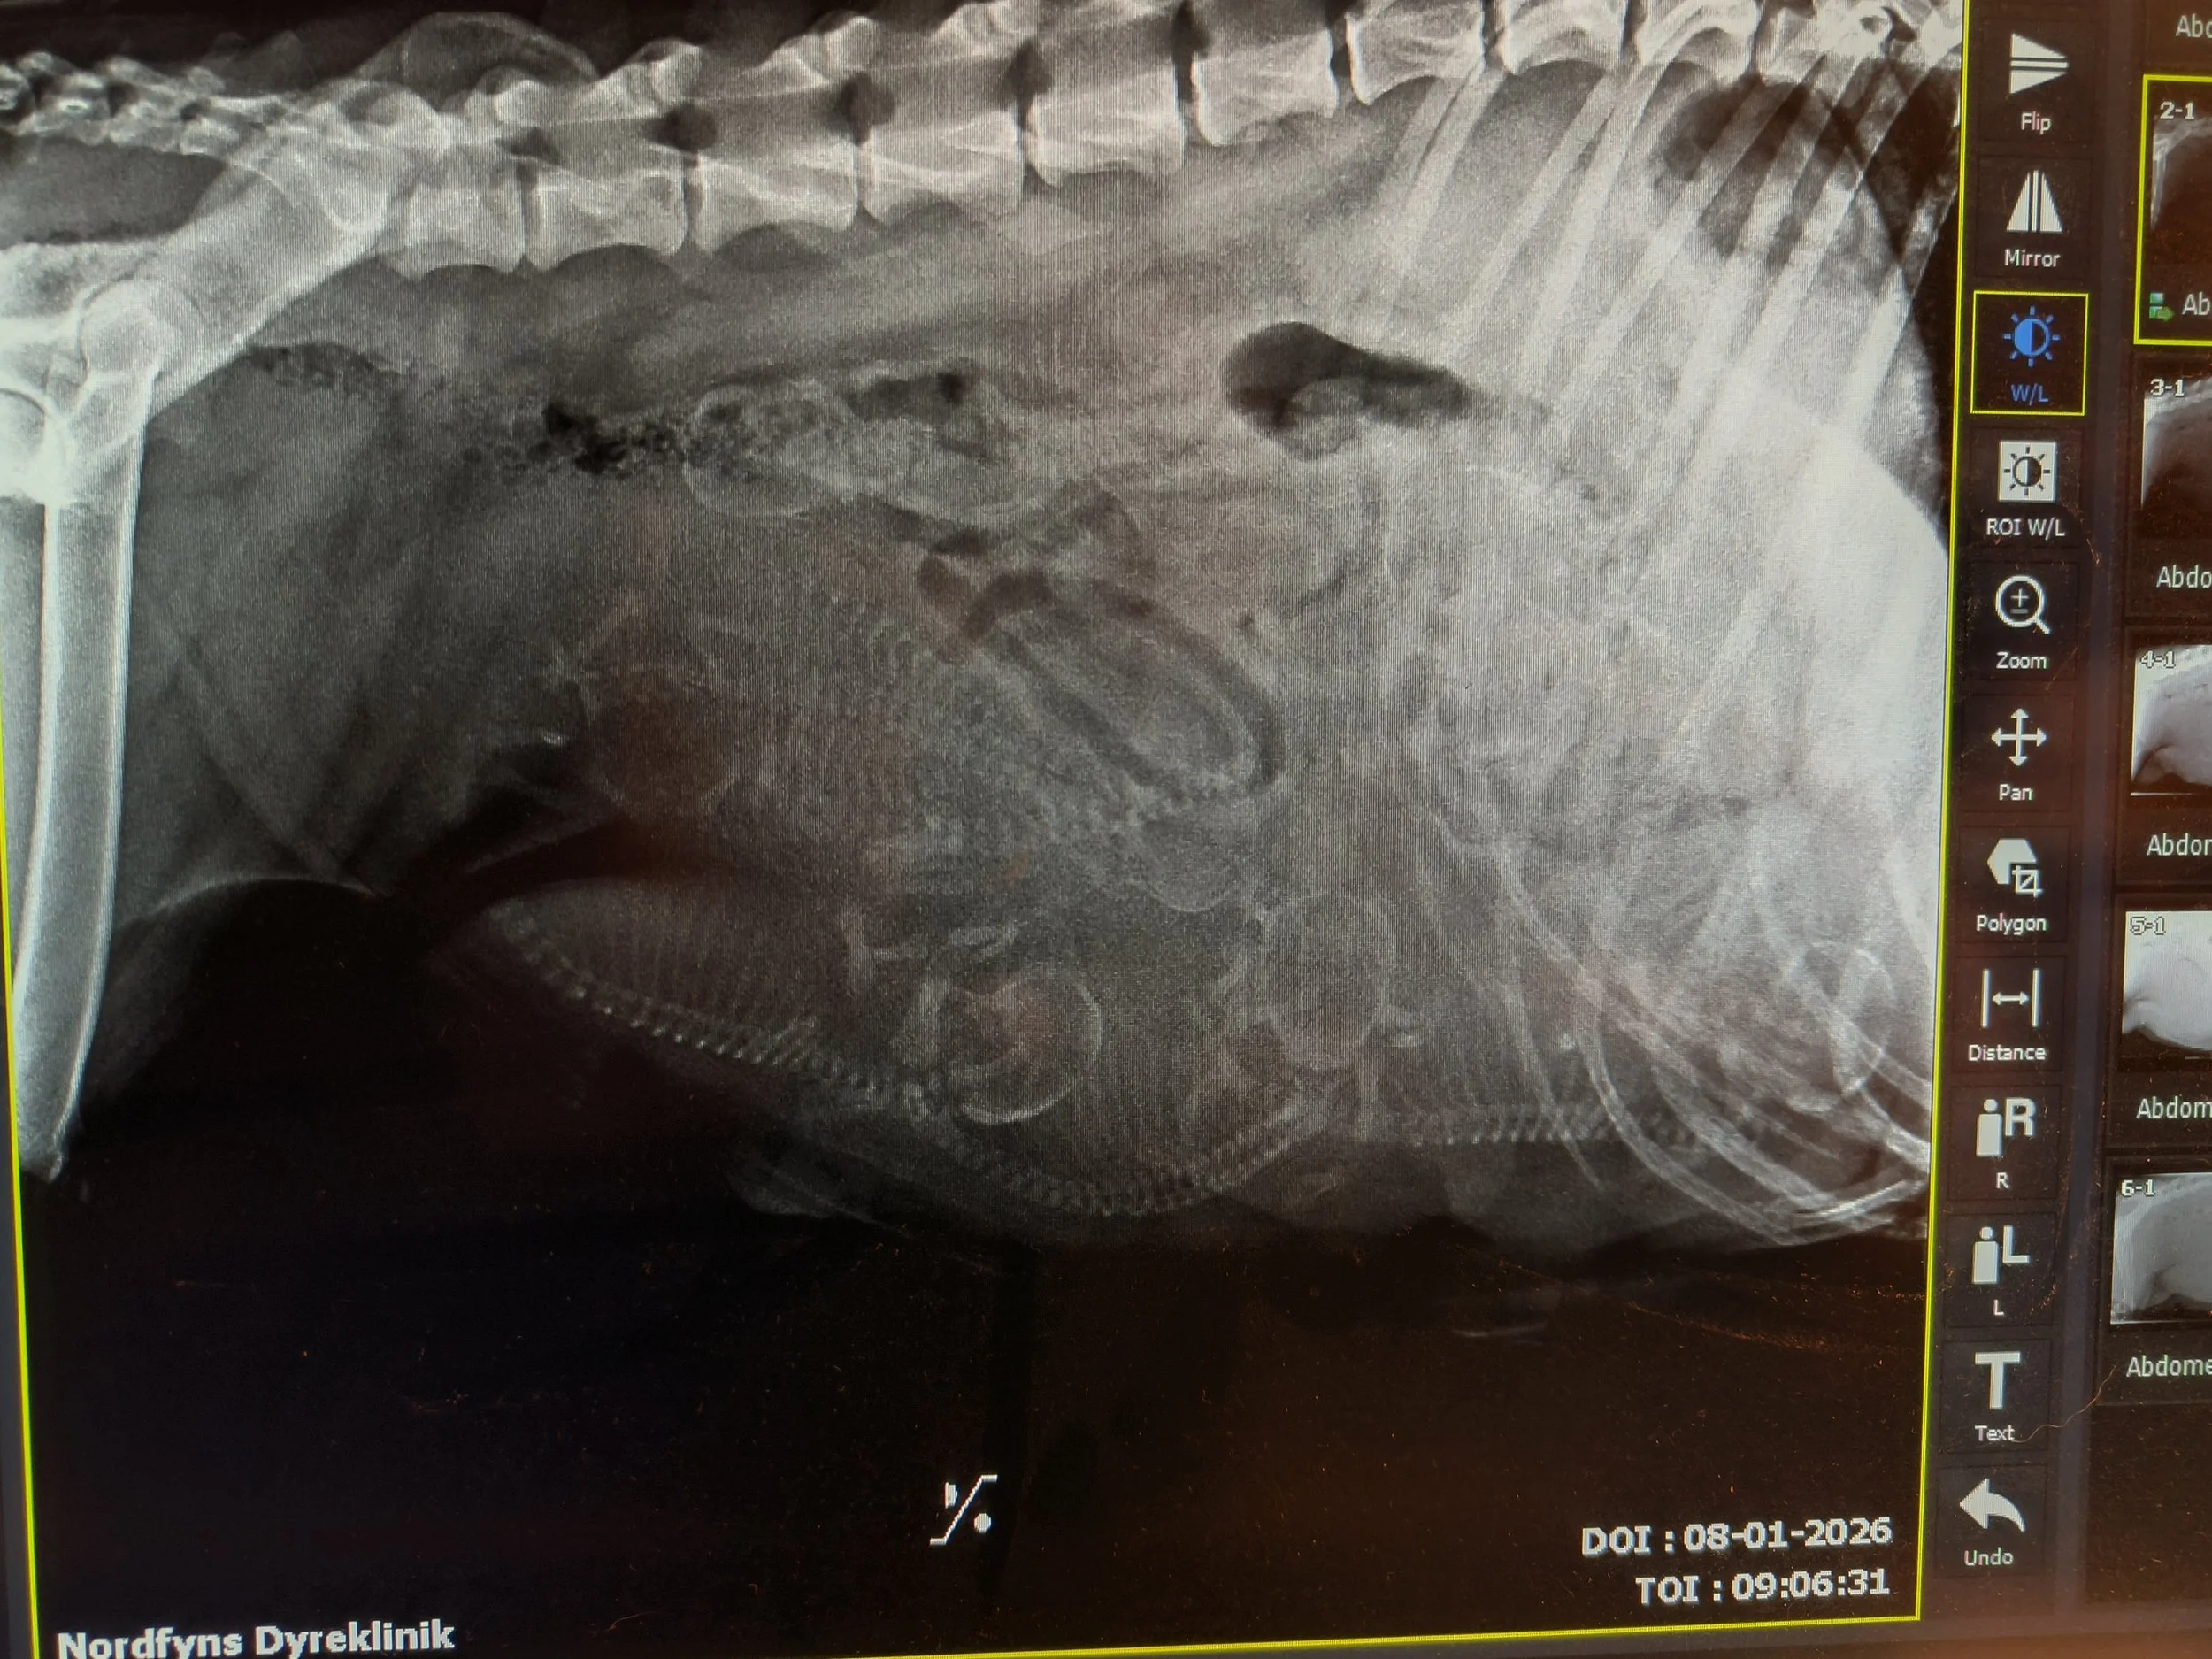

8. januar viste røntgen, at Juno ventede 7 hvalpe. Fødekassen var klar, og nu var det bare at vente på, at Juno også blev klar. 15. januar gik fødslen i gang, men da der pludselig kom grønt fostervand, måtte Juno af sted til dyrlægen, og det endte med kejsersnit. 2 hvalpe var døde 1 - 2 dage før fødslen, men Juno kom hjem med 5 dejlige hvalpe, 4 piger og en meget lille dreng. Selvom han fik tilskud lige fra starten og han suttede fint, tog han ikke på, og 6 dage efter fødslen måtte vi i samråd med dyrlægen lade vores lille Cliff sove ind - dyrlægen mener ikke, hans fordøjelsessystem var færdigudviklet. Det var hårdt, men nu ligger han begravet i haven sammen med de andre døde familiedyr. Og vi glæder os helt enormt over Cove, Caye, Cape og Crest. De trives og vokser synligt fra dag til dag. Juno er en meget dygtig hundemor og passer dem til UG.